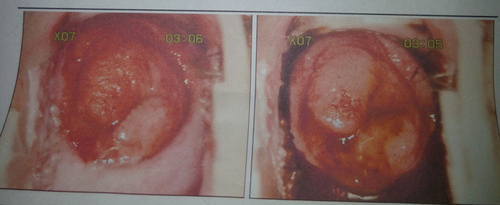

但由于疾病都是可能发生发展的,宫颈囊肿也不例外,如果导致宫颈囊肿发生的一些致病因素长期存在,就可能导致宫颈囊肿发展变大,甚至引起一系列的炎性病变表现,这个时候宫颈囊肿就可以发展变大,突出于宫颈口达到了阴道外口了,所以是可以用手直接触摸到的。

但是不要随意把手伸入阴道,以免加重感染。宫颈囊肿需要根据检查结果选择治疗措施,比较大的宫颈囊肿会影响生活,可以采取手术治疗。宫颈囊肿是良性病变,一般能够治愈。